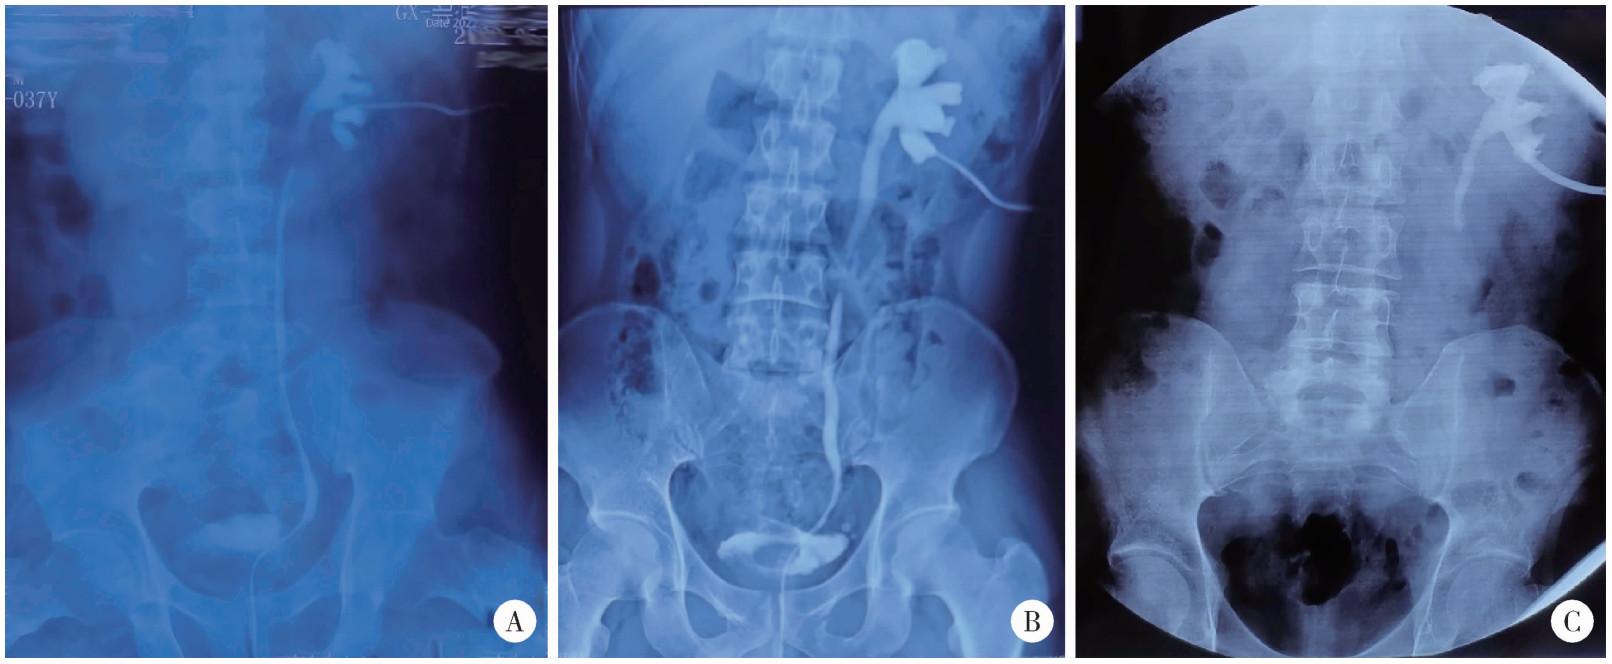

患者中位年龄56(18~74)岁。所有患者中,左侧和右侧输尿管狭窄各有35例,另有1例双侧狭窄。上段输尿管狭窄的患者最多(36/71, 50.7%),其次是下段输尿管狭窄(15/71,21.1%)和中段输尿管狭窄(9/71, 12.7%),另有11例(15.5%)患者为多发输尿管狭窄(图 1)。术前影像学测得中位输尿管狭窄长度为5.0(3.0~15.0) cm。术前最常见的症状是腰痛(28/71, 39.4%),其次是发热(19/71, 26.8%)、尿路刺激症状(5/71, 7.0%)、恶心(5/71, 7.0%)和血尿(3/71, 4.2%),另有24例患者(33.8%)无明显症状。术前超声检查显示积水程度轻度20例(28.2%)、中度24例(33.8%)、重度20例(28.2%),另有7例(9.9%)患者于北京大学第一医院泌尿外科就诊前已留置肾造瘘管,超声显示无积水。引流方式方面,9例患者曾留置输尿管支架管,35例患者接受肾造瘘置管,16例患者既有输尿管支架管留置病史,也曾留置肾造瘘管。10(14.1%)例患者曾接受球囊扩张或输尿管镜扩张等腔内治疗,13例(18.3%)患者曾接受修复重建手术。术前平均血肌酐(91.29±23.46) μmoL/L,平均估算肾小球滤过率(estimated glomerular filtration rate,eGFR)(82.19±19.97) mL/(min·1.73 m2)。

图1 结石相关输尿管狭窄

Figure 1 Stone-related ureteral strictures

A, short stricture; B, long stricture; C, extensive stricture.